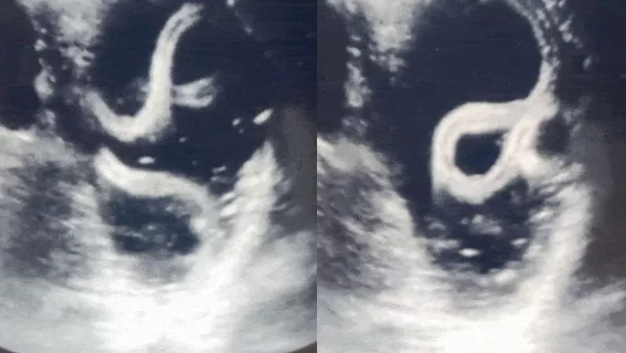

심지어 병원에서 검사를 하던 의사는 깜짝 놀라고 말았는데요. 그 이유가 바로 위장 속에 있던 큰 기생충이 살아서 움직이고 있었기 때문입니다. 기생충의 움직임이 초음파에 잡히는 등 의사도 처음 보는 일로 놀랐다고 합니다. 위장 속에서 살아서 움직이는 기생충을 봤다는 것은 충격 그 자체입니다.

병원에 찾았을 때 기생충의 여부는 초음파 검사를 통해 알 수 있고 위나 장에 기생충이 기생하여 살고 있을 때에는 반드시 알맞은 치료법으로 치료를 해야 하고 심한 경우에 수술을 진행할 수도 있습니다.